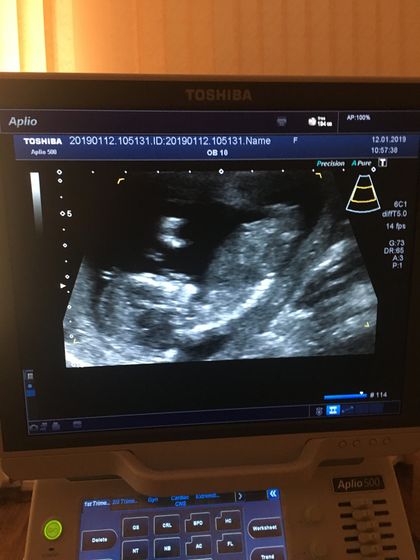

Сегодня ураааа!!! Был первый скрининг:) сделали узи, взяли кровь :) развивается немного быстрее :) обычно недели считала по средам недели, теперь буду по понедельникам:) получается завтра уже 14 неделек:)☺️ 7.9 см от копчика до темечка:)

Сказала « вроде мальчик»